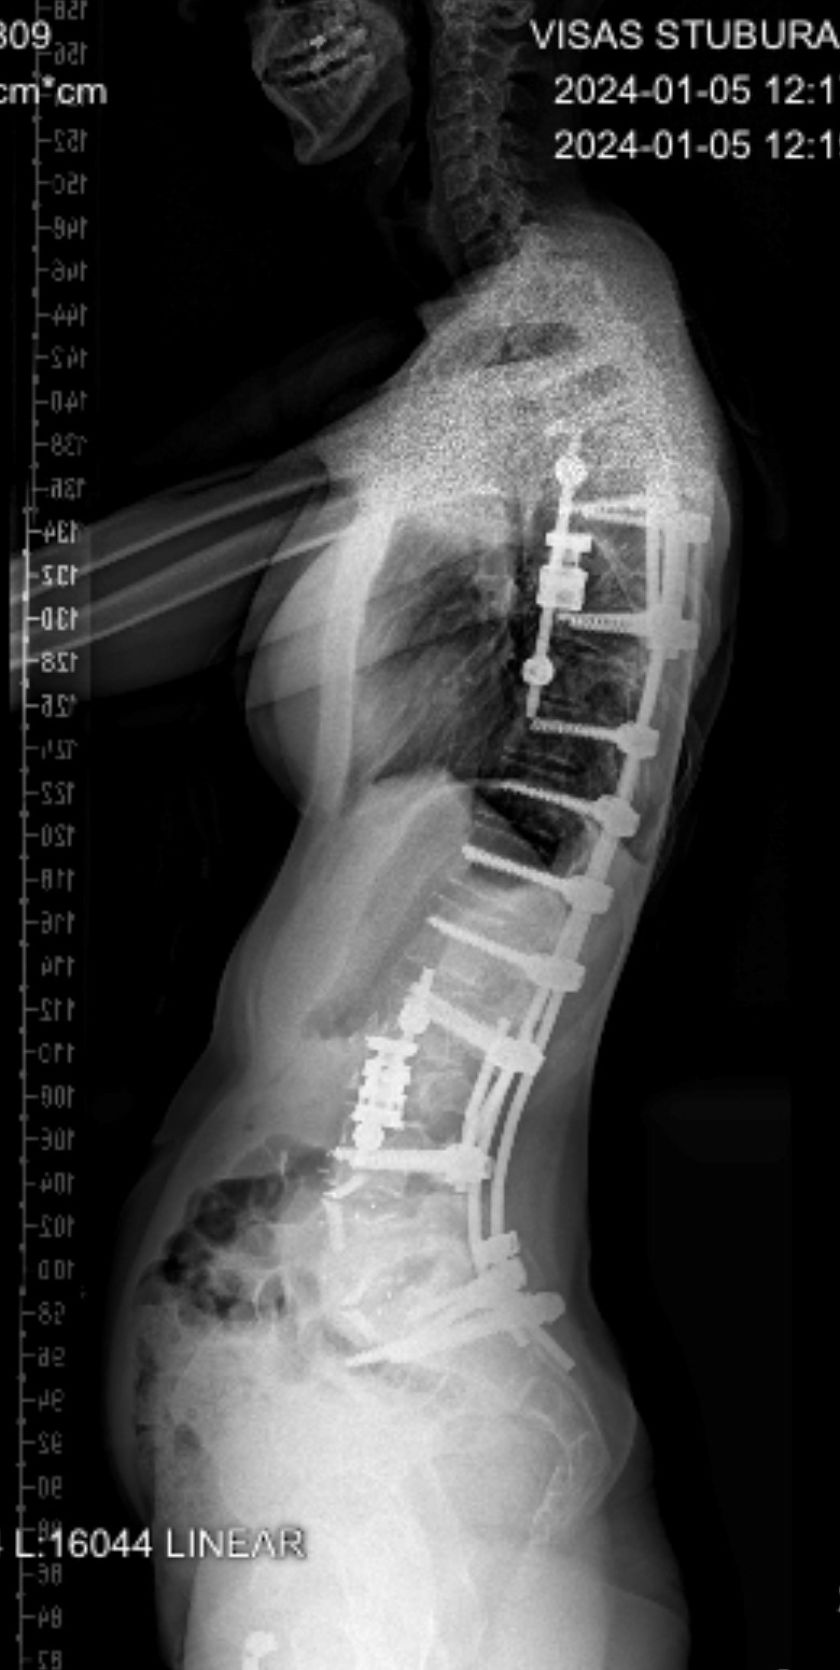

Pacientės stuburo slankstelių lūžio gydymo odisėja prasidėjo prieš trejus metus. Trauma įvyko Belgijoje, vienoje iš ligoninių atliktos dvi operacijos ir pacientė išleista į namus. „Žaizda gijo sunkiai, po mėnesio vėl patekau pas chirurgus – žaizdą dezinfekavo ir užsiuvo, – pasakoja moteris. – Jie darė prielaidą, kad tai buvo paviršinė infekcija ir išsamesnių tyrimų nusprendė atsisakyti.” Ir po šios operacijos žaizda gijo sunkiai. Moteris ir jos artimieji pasitikėjo medikais ir visa sveikatos sistema: „Per dvejus metus Belgijoje man buvo atliekami periodiniai kompiuterinės tomografijos tyrimai, deja, ten dirbantys medikai nesugebėjo pastebėti infekcijos.”

Praėjusių metų vasarą žaizdai pūliuojant pacientė kreipėsi į VUL Santaros klinikų Skubios pagalbos skyrių: „Čia ir paaiškėjo, kad su infekcija gyvenau dvejus metus, o Belgijos chirurgai šitą faktą tiesiog ignoravo. Tai buvo ir psichologiškai, ir fiziškai sunki patirtis. Anot medikų, mano sveikatos būklę galima buvo palyginti su tiksinčia bomba. Santaros klinikose man atliko visus reikiamus tyrimus, rado tą patį auksinį stafilokoką ir skubiai paguldė į ligoninę. Gydytoja Ona Lapteva pranešė, kad stuburo implantai infekuoti ir likęs tik vienas pasirinkimas – juos pakeisti naujais, – pasakoja pacientė. – Belgijos gydytojams pranešiau apie savo situaciją. Jie pasakė jokiu būdu neliesti nugaros smegenų, nes didelė tikimybė, kad operacija nepavyks ir aš galiu nevaikščioti…” Po 9 savaičių gydymo moteris džiaugiasi rezultatu: „Nors daug skausmingo, sunkaus teko patirti, išgyventi, visgi galiu pasidžiaugti, kad susipažinau su nuostabiais žmonėmis – gydytojais bei visu personalu – ir supratau, kaip gera savo šaly turėti tokių profesionalių ir dėmesingų specialistų.”